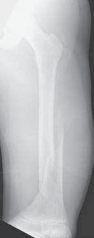

Chapter 33 Repair of Congenital Pseudarthrosis of the Tibia With the Williams Rod Perry L. Schoenecker and Ma…